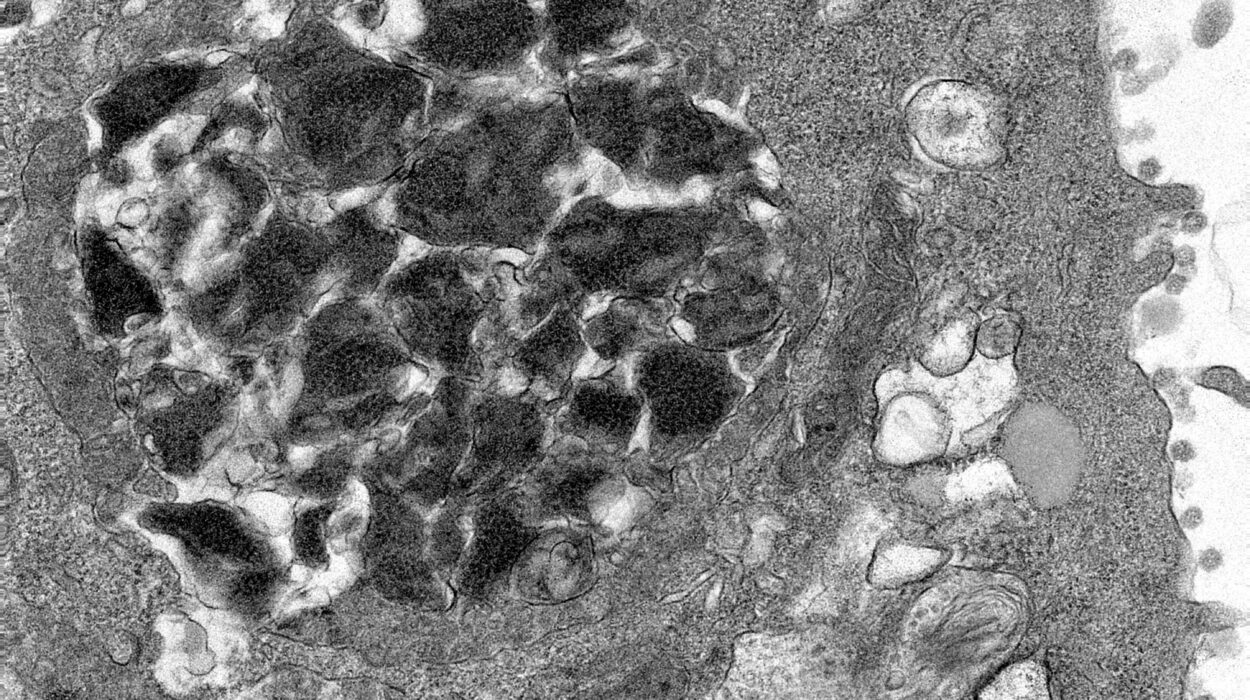

P4HA1, a prolyl hydroxylase enzyme, typically contributes to collagen production, a vital component of the extracellular matrix. However, it is now evident that its role extends to regulating the metabolism and function of immune cells, particularly T cells. In the tumor microenvironment (TME), P4HA1 is upregulated in exhausted CD8+ T cells, significantly impairing their ability to generate energy and function properly. This disruption of energy production leads to weakened immune responses and an inability of T cells to form a lasting anti-cancer memory, an essential aspect for long-term immunity and protection against tumor relapse.

The A*STAR GIS study found that the expression of P4HA1 is significantly elevated in T cells within solid tumors, leading to energy dysregulation, immune exhaustion, and poor T cell function. This impairment is especially problematic because it prevents immune cells from adapting and effectively combating cancer in the long term. Furthermore, P4HA1 levels in blood immune cells were found to increase as cancer progresses and relapse occurs. These findings suggest that P4HA1 not only weakens the immune system’s defenses but can also serve as a potential biomarker for tracking cancer progression, immunotherapy responses, and relapse.